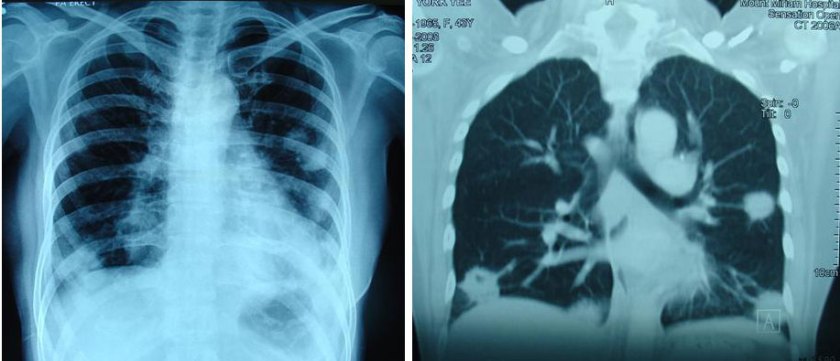

By February 2008, failures started to show up again. A CT scan on 13 February 2008 indicated:enlarging pulmonary nodules ranging from 0.5 to 2.2 cm.

Six months later, 19 August 2008, CT scan indicated pulmonary nodules are increasing in number and measure from 0.5 to 5.0 cm. Subcentimeter mediastinal nodes are also seen.

In October 2008, Yee suffered right arm pain and there was palpable swelling in the right collarbone. CT scan on 13 October 2008 showed more serious disease progression:

- fibrosis in the right axilla.

- an irregular ill-defined node in the right infraclavicular region, approximately 2.0 cm.

- another small right supraclavicular node, 0.7 cm is also present.

- medistinal nodes,size slightly increased from the last CT examination.

- pulmonary masses and nodules are enlarging. The largest mass, in the left lung is currently 5.6 cm. Other lesions measure from 1.0 to 4.8 cm.

- A new hypodense lesion, approximately 1.0 cm is now seen in Segment 7. This is suspicious of liver metastasis.